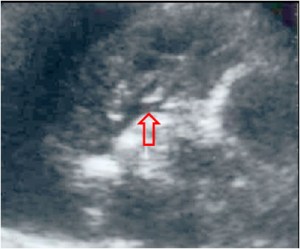

SIGNO DE LA ALMOHADILLA EPICÁRDICA (O SIGNO DE LA GALLETA OREO)

Signo de derrame pericárdico en la radiografía lateral de tórax. El derrame aparece como una banda curva de densidad agua que separa las capas grasas pericárdicas visceral y parietal a nivel retroesternal bajo.

La radiografía posteroanterior de tórax del mismo paciente muestra el aumento de tamaño de la sombra cardíaca con la morfología característica del derrame pericárdico (corazón en “tienda de campaña”). A la derecha, la imagen de TC con el derrame pericárdico (D) separando las capas grasas pericárdicas visceral (V) y parietal (P).

En la literatura en inglés, este signo es llamado «oreo cookie sign» por el aspecto de las capas hipo, hiper e hipodensa.